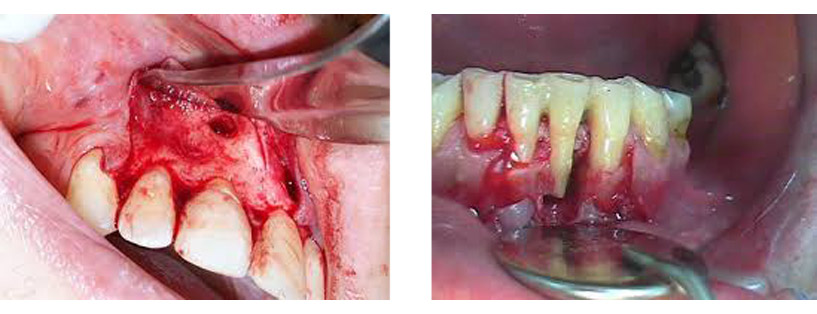

Χειρουργική αφαίρεση κύστεων των γνάθων

Στα οστά της άνω και κάτω γνάθου συχνά δημιουργούνται κοιλότητες που περιβάλλονται από μία μεμβράνη και περιέχουν υγρό, είναι απολύτως καλοήθεις και δημιουργούνται αυτόματα ή από νεκρά δόντια. Η χειρουργική αφαίρεση σε περιοχές με αυξημένο πάχος του εξωτερικού φλοιού του οστού μπορεί να απαιτήσει εκτεταμένη αφαίρεση αυτού και πιο σύνθετες μορφές αποκατάστασης.

Χάρη στις σύγχρονες αναπλαστικές τεχνικές μπορούμε παράλληλα με την αφαίρεση μίας κύστης να αναγεννήσουμε και τους κατεστραμμένους ιστούς της γνάθου. Με ένα τέτοιο τρόπο μπορούμε να διορθώσουμε τη βλάβη και να επαναφέρουμε τη γνάθο στο αρχικό, φυσιολογικό της σχήμα.